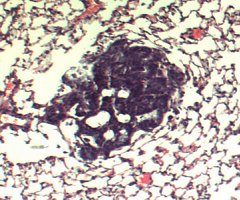

Celiac Disease Research - Mouse Model